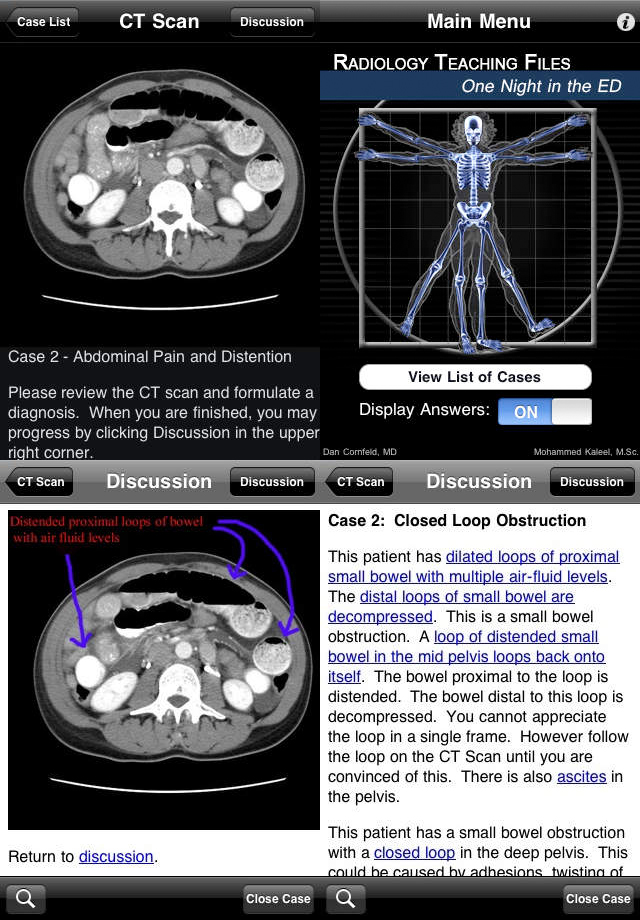

Radiology 2.0 One Night in the ED

呈现互动式教学,拥有一系列案例,以模拟PACS工作站的方式让用户浏览CT图像,针对每个病例有更深入的探讨,附有病理学家和相关的诊断结果。能教会用户解读CT扫描,适用于所有医学界人士,且免费。所有内容能线下浏览,掌上阅读,方便碎片化时间学习。 有以下两个系列—— Volume 1. 急诊室的一夜(One Night in the ED): 教学软件让用户学习急诊病理学中的CT扫描图像,目前包括急性胸部,腹部,盆腔病变案例,每一个病例后重要的结论有箭头、圆圈等彩色标示。该卷包含7000多幅高质量的图片与几百幅网页文件。

Radiology 2.0 Pregnant Appendicitis

第二卷加入了图片放大和平移功能,也支持纵向和横向的观察,主要呈现阑尾炎的MRI图像,病例来源于临床孕妇,收集41例引起右下腹疼痛的疾病,包括阑尾炎、肠梗阻、卵巢扭曲、肾盂肾炎等。